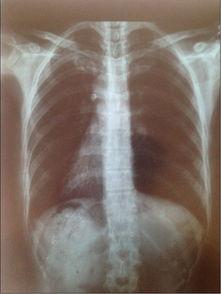

首先,你得知道,胸片是一种医学影像检查,主要用于检查胸部器官,如心脏、肺部等。而2023年的胸片爆料,可是透露了不少关于我们身体健康的新信息。

据《健康时报》报道,2023年的胸片技术有了很大的突破。首先,分辨率更高了,这意味着医生可以更清晰地看到胸部器官的细节。这样一来,对于早期发现肺部疾病,如肺癌等,就有了更大的帮助。

你知道吗?现在很多医院都开始使用人工智能技术来辅助诊断胸片了。据《医学论坛报》报道,2023年的AI辅助诊断技术已经非常成熟,可以快速识别出肺部结节、肿瘤等异常情况。这样一来,医生就能在第一时间发现潜在的健康风险,为患者争取更多治疗时间。

除了AI辅助诊断,3D重建技术也是2023年胸片的一大亮点。这项技术可以将二维的胸片转化为三维图像,让医生更直观地了解患者的胸部结构。这样一来,对于一些复杂病例的诊断,如心脏疾病等,就有了更多的帮助。